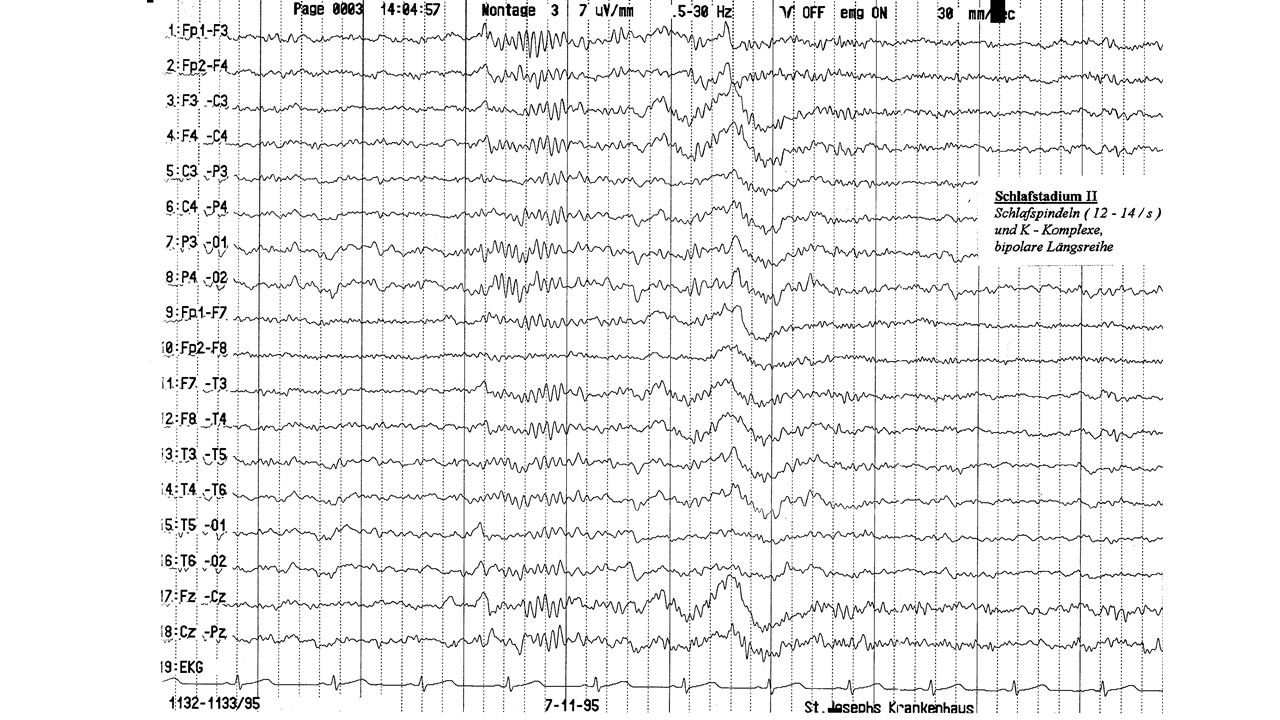

folie634.jpg